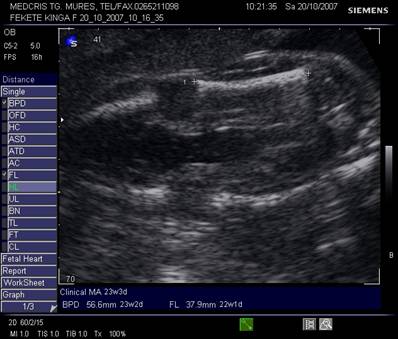

Masurarea oaselor lungi

confirma dezvoltarea fetala normala, detecteaza displazia scheletala, ajuta la diagnosticul de microcefalie, retard de crestere intrauterina, suspiciunea unor sindroame genetice.[2,3]

Parametrii constau in masurarea partii osificate a oaselor lungi, ce constau din diafiza si metafiza. Epifiza distala si proximala, ca si curbatura oaselor lungi, sunt ignorate.

Tehnica cuprinde o asezare perpendiculara a sondei pe axul lung al oaselor, cu evidentierea capatului osului, fara a fi superpozabil pe cele din jur.[7]

Fig. nr.201. Masurarea lungimii femurului ( FL)